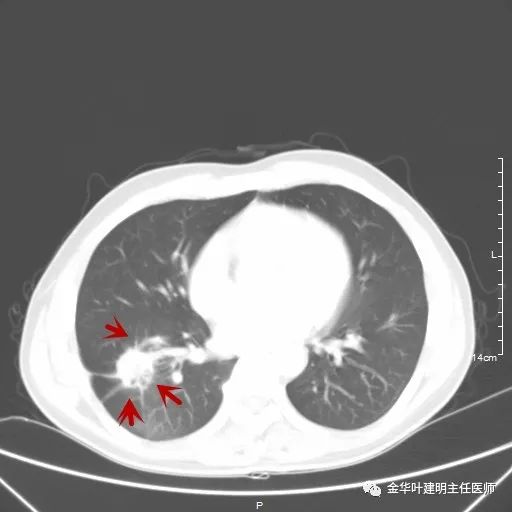

如果选取肿瘤所在的层面来看,则是以下图像:

以上是肺窗,见右肺下叶实性占位,有毛刺、浅分叶、膨胀性,血管征等,是较为典型的恶性肿瘤。